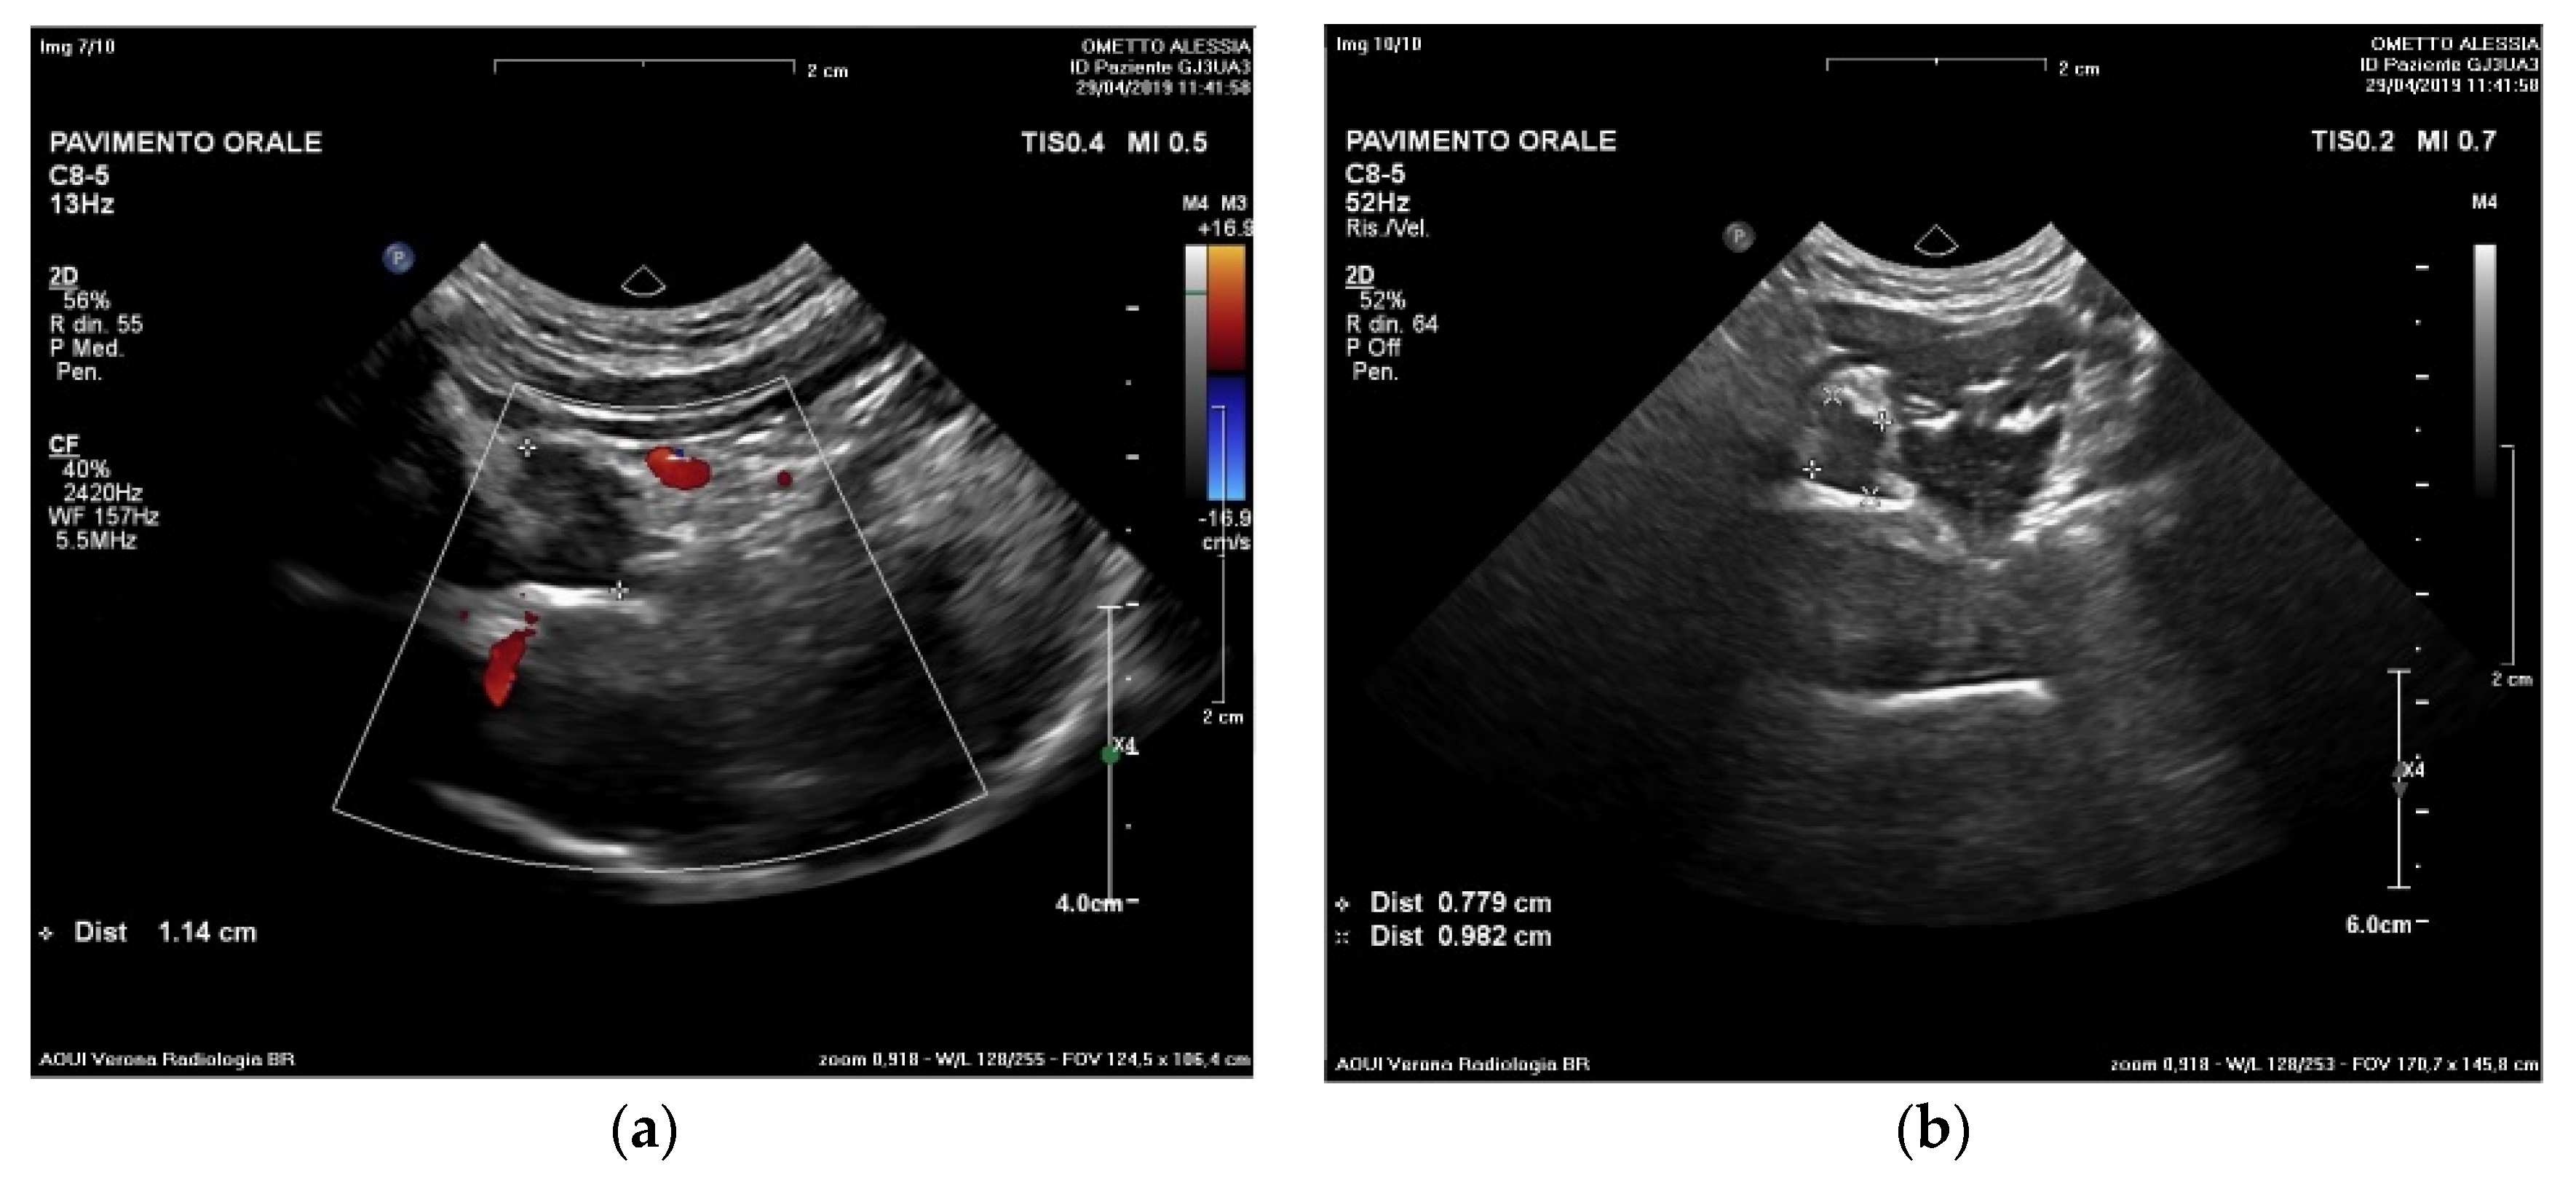

2. Materials and Methods